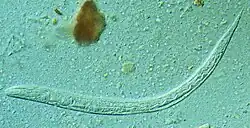

L'anguillule parasite de l'intestin est une minuscule femelle parthénogénétique strongyloïde, très mince et longue de 2 à 3 mm. D'autres formes adultes, mâles et femelles stercoraux (qui concernent les excréments) existent seulement à l'état libre ; elles sont rhabditoïdes et atteignent 1 mm pour la femelle, un peu moins pour le mâle.

L'association avec l'ankylostomose rend fréquemment le diagnostic délicat. Il est très difficile de distinguer les larves d'ankylostome des larves strongyloïdes. Toute diarrhée au long cours, évoluant par crises successives, avec éosinophilie commandera la confirmation parasitologique par examens de laboratoire. Le diagnostic repose sur l'identification au microscope des larves (rhabditoïdes et parfois strongyloïdes) dans les selles (examen parasitologique des selles) ou dans le liquide duodénal. L'examen des prélèvements est nécessaire, mais pas toujours suffisant, parce que l'examen direct des selles est relativement peu sensible et nécessite d'être répété sur plusieurs examens. Le délai de positivité de ces examens après contamination peut atteindre un mois[2].